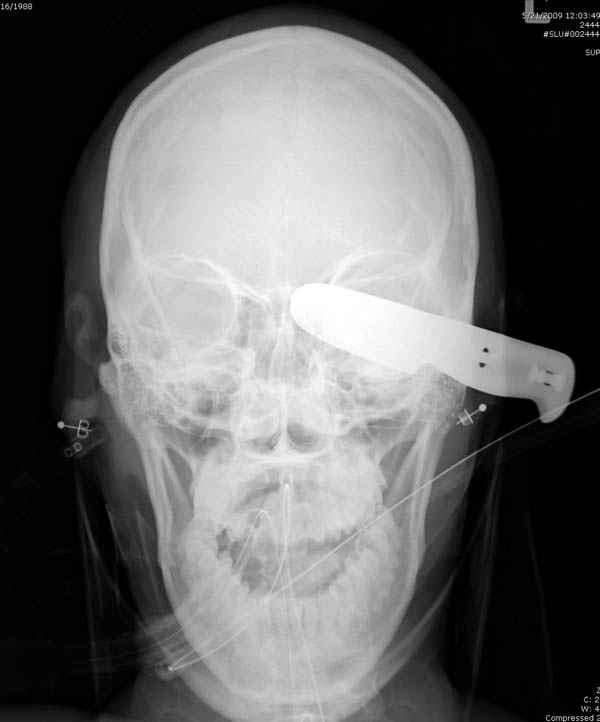

В своих выступлениях я рассказывал, что наши центры в мирное время по пенетрирующим травмам не уступает Ираку или Афганстану, и вот недавно к нам поступила больная 22 лет, травма "ножом в глаз" от бывшей подруги нынешнего "бой френда".

При поступлении в сознании, жаловалась на неприятные ощущения в глазнице.

По протоколу сделаны все необходимые исследования: рентген, ангиограмма с 3Д реконструкцией, где обнаружили что все жизненно важные сосуды не задеты, даже некоторые "сидят" изгибаясь на ноже.

Одним махом нож удалить не удалось, пришлось раскачать и потом двумя руками удалили нож. Рана без кровотечения, обработана и зашита.